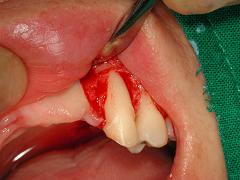

이가 많이 흔들리면 그때는 이미 늦기때문에 심해지기 전에 꼭 치석을 제거하는 스케일링을 하셔야 합니다, 아래 그림은 잇몸을 절개하여 잇몸속에 숨어있는 치석을 나타낸 그림입니다.

그림2와 3은 치은연하에 있는 치석을 수술을 통하여 제거한 그림입니다.